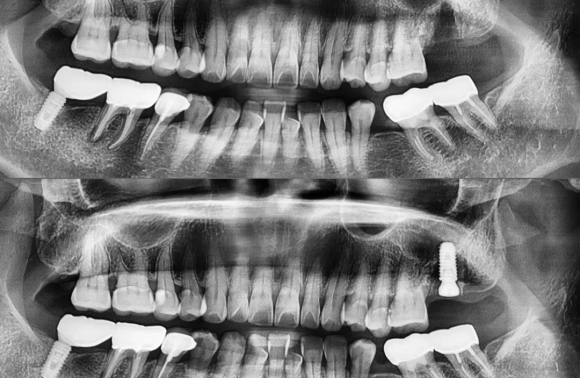

2022.2.21 구치부 발치 후 즉시 임플란트/ 상악동+뼈이식 케이스 #상도동에서임플란트가장많이하는치과

2022.2.21 구치부 발치 후 즉시 임플란트/ 상악동+뼈이식 케이스